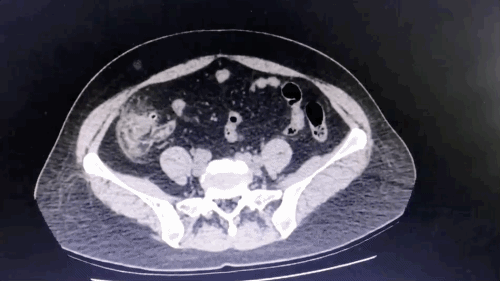

图片

病例二:患者腹部 CT

与前一个病例类似,CT 示盲肠周围脂肪间隙模糊,盲肠壁多个囊袋状突起,背侧两憩室内为高密度影,腹侧一憩室内为气体影。阑尾向下指向盆腔,腔内粪石及积气,但周围无明显炎症表现。

诊断:盲肠憩室炎,阑尾腔内粪石、积气。